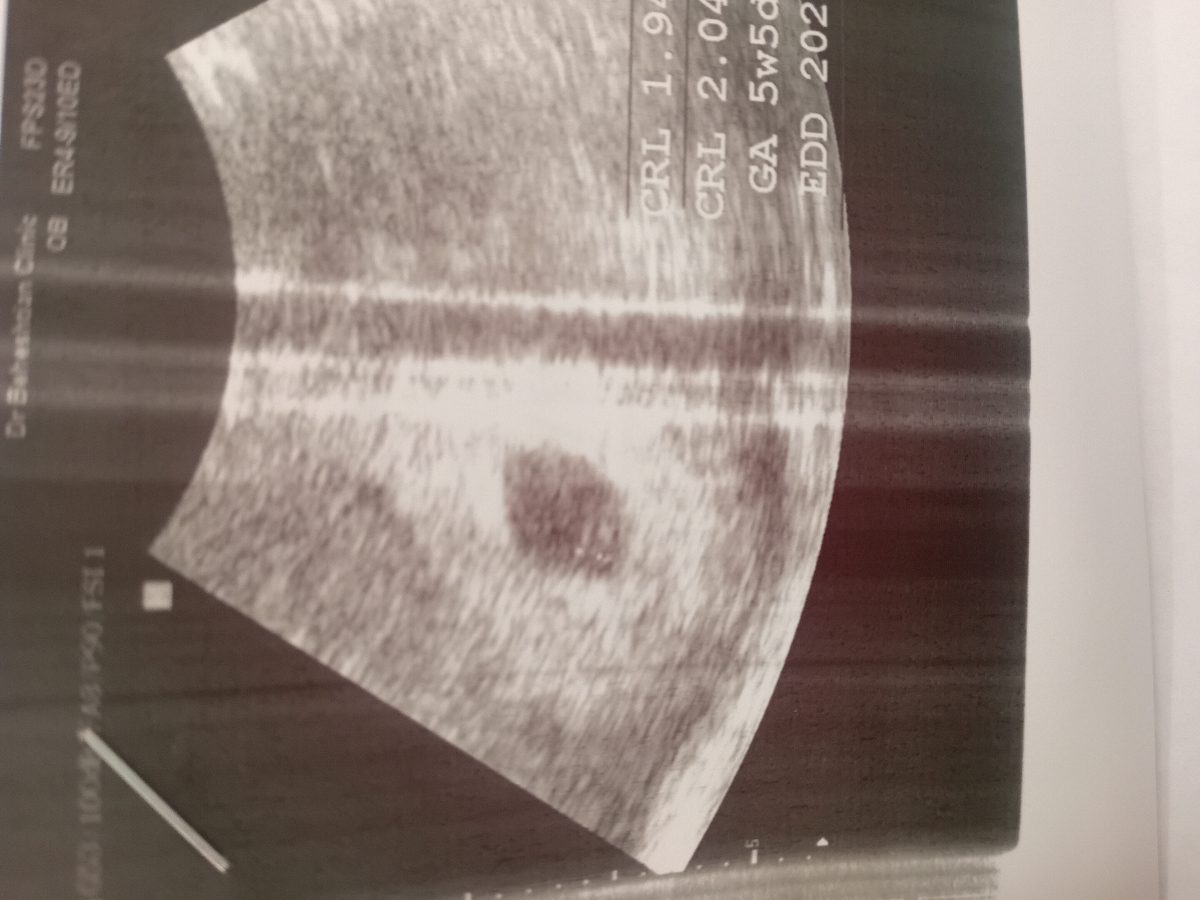

گف کیسه زرده هس فتال پلم هس فقط ضربانشو نمی تونم دقیق متوجه بشم ،شک دارم گف برا ضربان زوده ۵ هفته و ۵ روزی،حالا دیکه نمیدونم دقیقه یا ن

ن گف کیسه زرده و فتال پل هست

داخل برگه زد CRL مساوی۲ م م